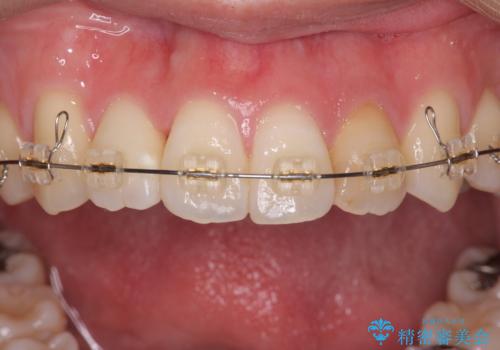

引っ込んだ前歯を並べたい マウスピースと部分ワイヤーのコンビネーション矯正

- 引っ込んで生えてしまっている前歯を並べたい、と矯正治療を希望され来院されました。

まずマウスピース矯正インビザラインシステムで、引っ込んだ歯が並ぶためのスペースを作ったのち、部分ワイヤー矯正を行い短期間での配列を計画します。

マウスピース・ワイヤーそれぞれの長所をうまく活かすことで治療期間の短縮が可能となります。

このように前歯の部分ワイヤーは引っ込んでしまった前歯や がたつきを素早く改善することができます。